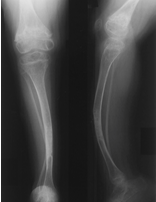

osteogenesis imperfecta as characterized by bowed long bones